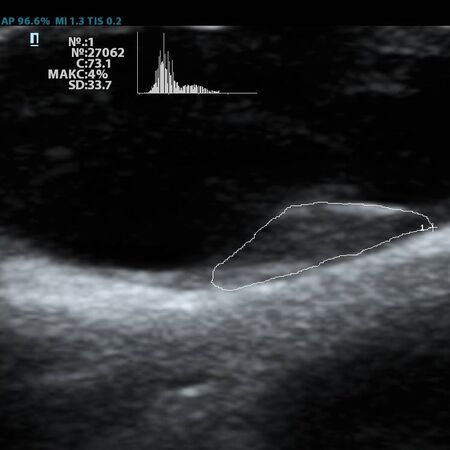

Современное решение – компьютерный анализ структуры бляшки. Ультразвуковая система экспертного класса Mindray DC-8 способна провести программный анализ полученного изображения бляшки и дать количественную оценку её структуры. Для этого используется показатель GSM – Grey Scale Median. Прибор рассчитывает медиану по показателям серой шкалы в выделенной зоне и выдает данные в виде графика распределения эхогенности и числовых данных для количественной оценки. Таким образом, исследование становится более объективным и воспроизводимым, снижается зависимость от оператора (человеческого фактора).